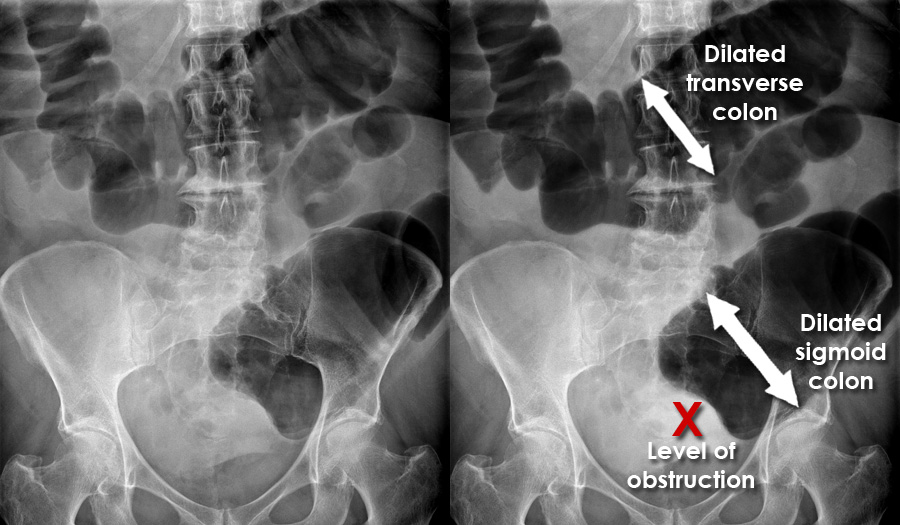

(肠梗阻X光示意图)

常规的入院检查,发现她感染了幽门螺杆菌,有严重小肠梗阻、盆骨压迫、高血压。医生百般劝说下,她勉强同意吃了抗生素和降压药。

第一个就是常年消化不良、腹痛。9年来,因为钙化的石胎压迫大小肠,她一吃多就吐,严重的时候吐胆汁,所以不敢多吃,导致营养不良,体质很弱。

一边担忧诅咒,一边又说不怕死,病人的肠梗阻情况越来越严重,却依然反复拒绝手术,最后执意出了院。14个月后,因为肠梗阻导致极度营养不良,她在美国去世,几乎是活活饿死。